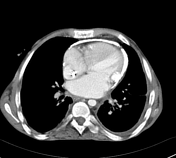

52세 남성이 18개월 전부터 서서히 증가하는 호흡 곤란, 하지 부종 및 지속적인 피로감을 호소하며 내원하였다. 혈압은 110/68 mmHg, 맥박은 분당 78회로 측정되었다. 환자의 흉부 X선 및 CT 영상을 검토한 결과, 다음과 같은 치료 방법을 고려하였다. 가장 적절한 치료 방법은?

흉부 X선과 CT 영상에서 pericardial calcification 소견으로 교착성(또는 압축성)심막염이다. 심낭제거술(pericardiectomy)가 근본적인 치료이다.

이 환자에서 심낭 석회화가 존재한다는 것은 질병이 염증 단계를 넘어 더욱 만성적인 섬유증 또는 석회화 단계로 진행되었음을 의미하며, 수술적 치료(pericardiectomy)가 더 적절하고 결정적인 치료 옵션이 됩니다.